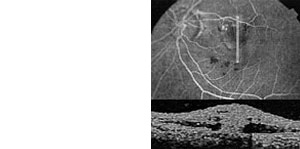

OCT - Optische Kohärenztomographie

www.zeiss.de: Spectral_Domain.pdf